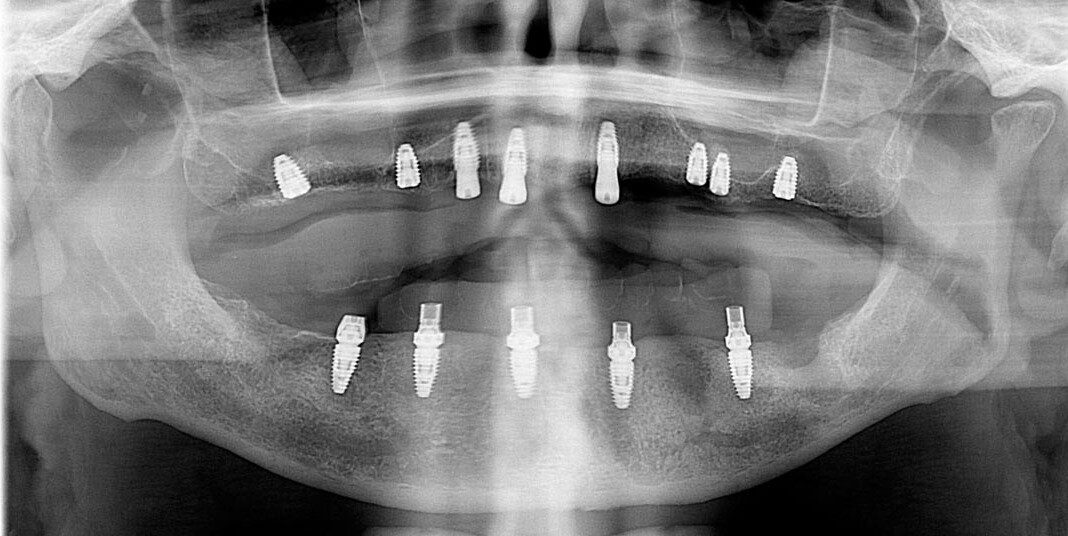

Pre-op, Panoramic x-ray. Note: Excellent bone in the upper front, reasonably good bone everywhere else.

Lower teeth extracted, some bone removal lower, 8 upper implants, 5 lower implants, lower immediate temporary bridge.